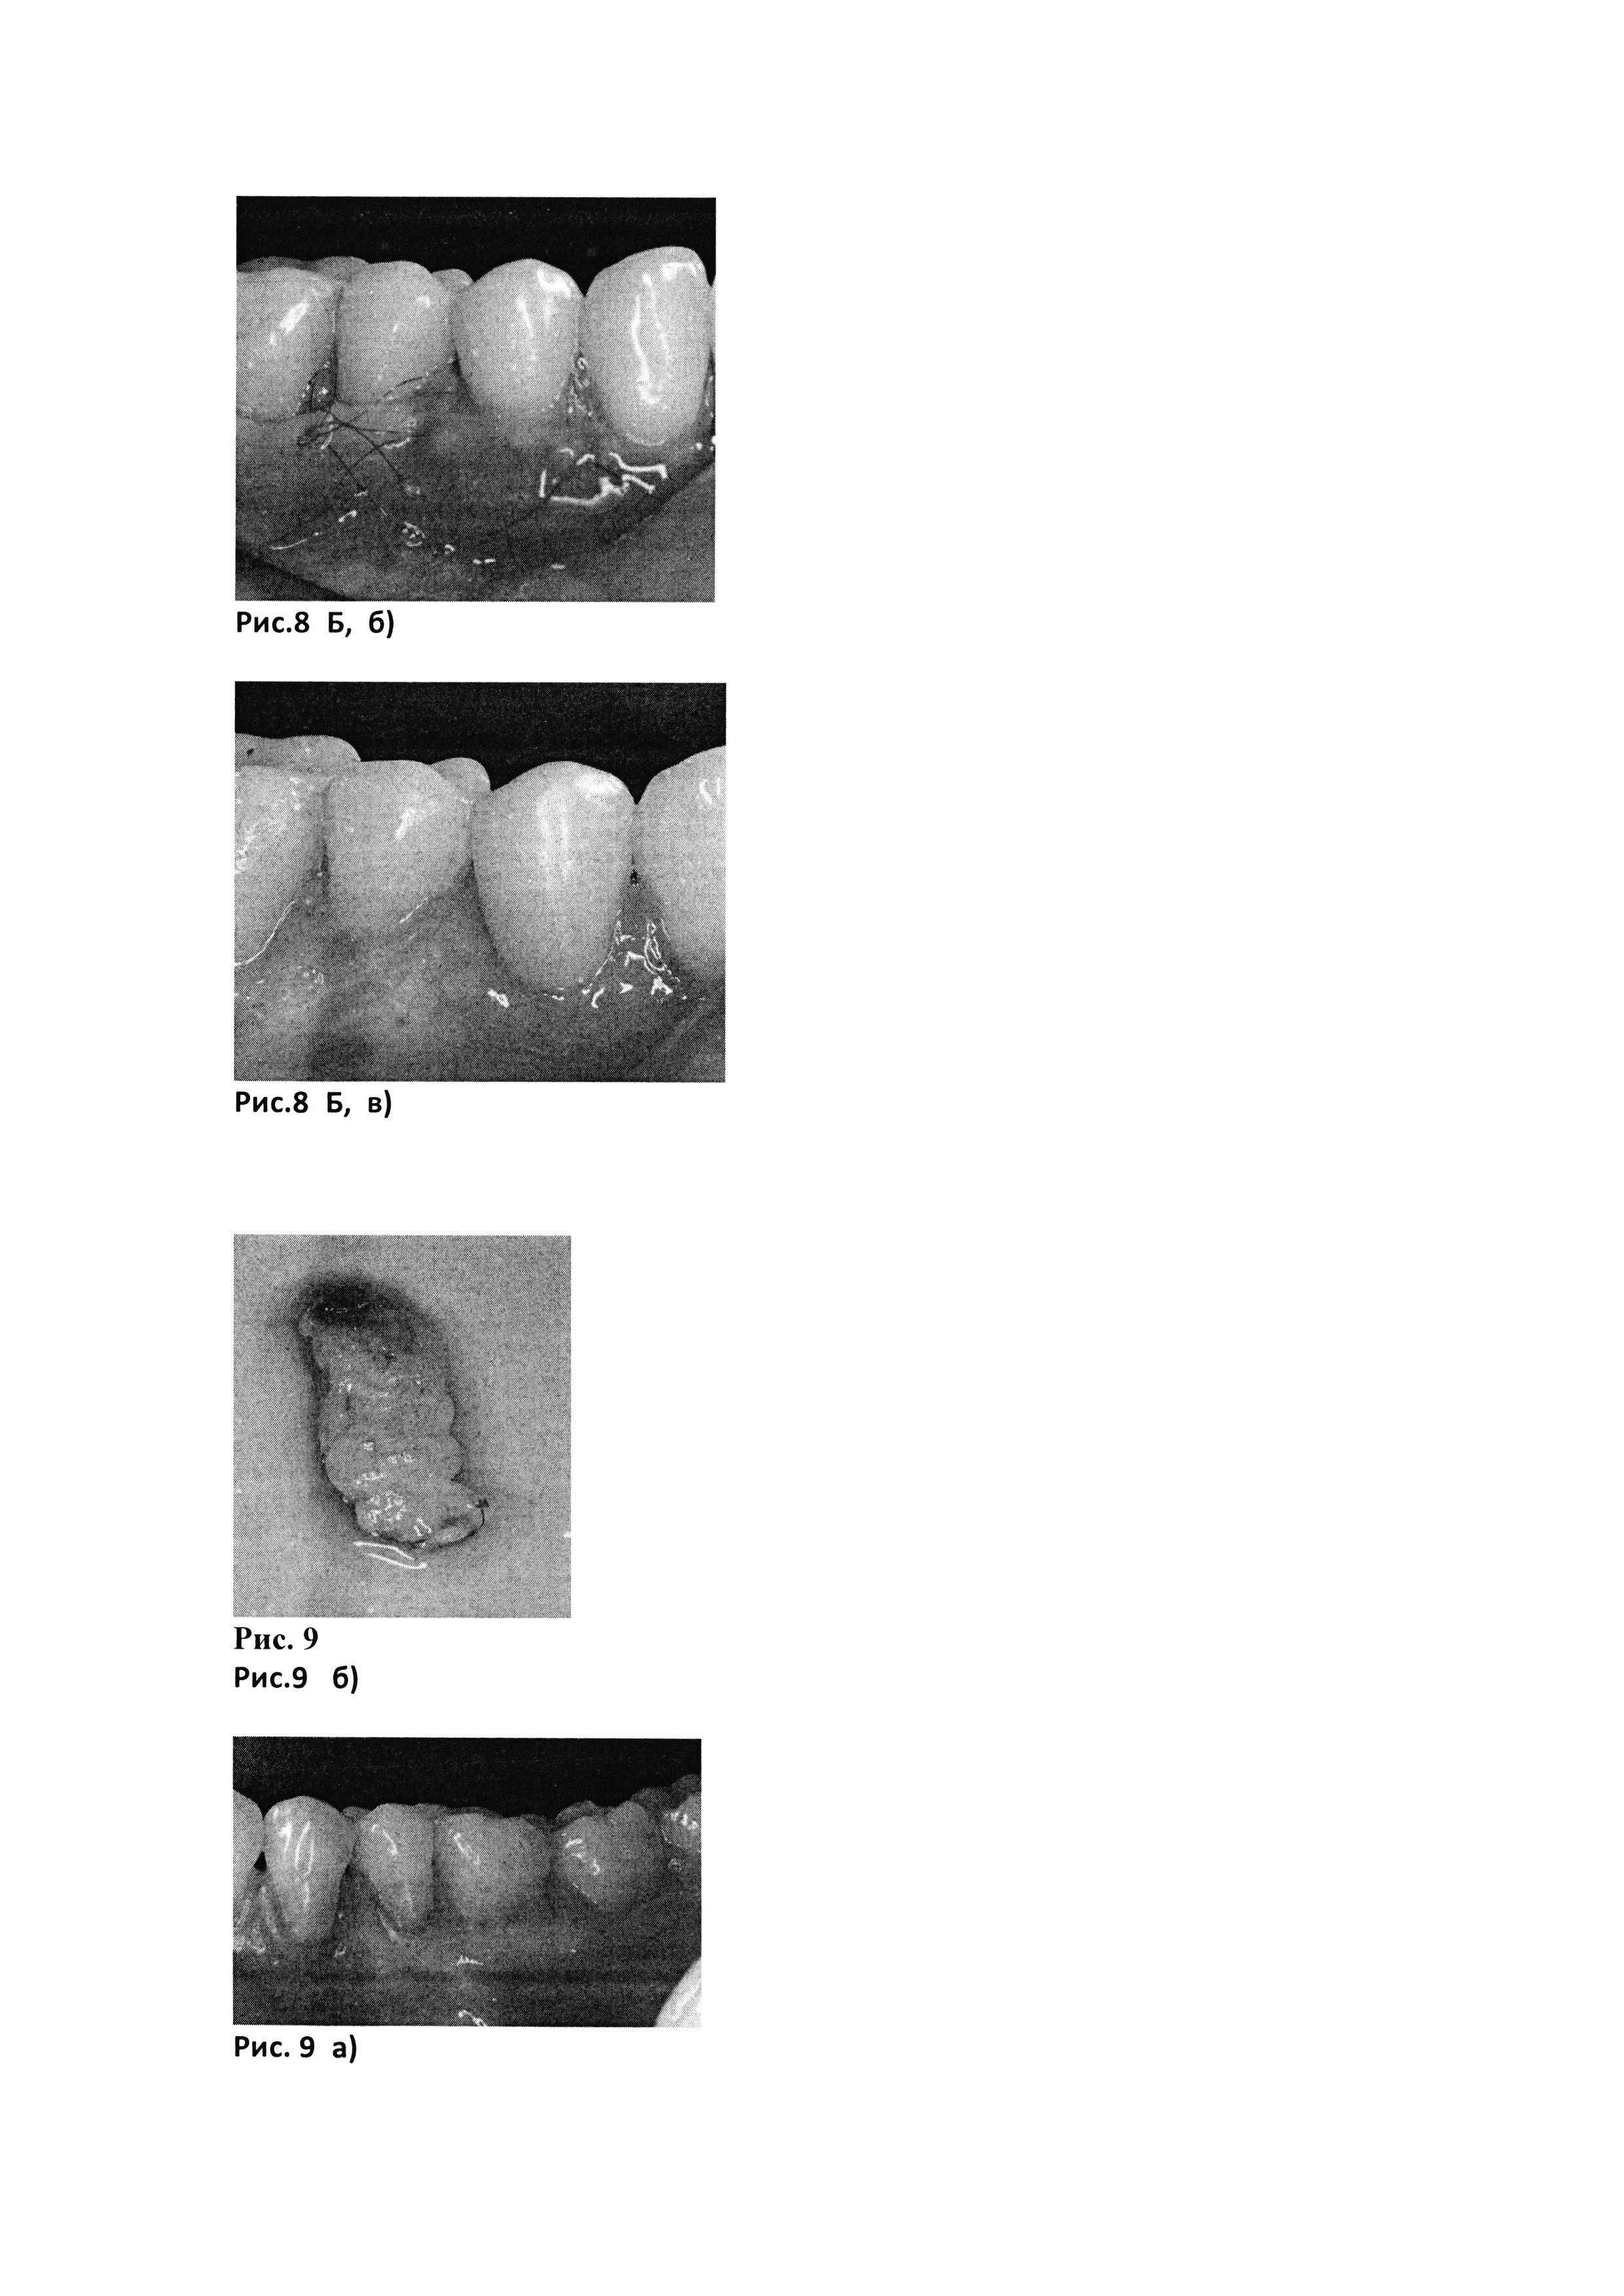

Рис. 8. Клинический пример №1. Б. Хирургическое вмешательство в области рецессий десны с применением PRF-мембраны + аутоФС (а, б, в).

[36]

Рис. 8. Б, а) до лечения

[37]

Рис. 8. Б, б) через 12 дней после операции

[38]

Рис. 8. Б, в) через 3 мес после операции

Рис. 9. Клинический пример №2.

[40]

Рис. 9, б) Биотрансплантат, представляющий собой PRF-мембрану (полученную с помощью центрифуги Scilogex, USA (РУ №РЗН 2015/3442) с интегрированными в нее аутоФС пациентки.

Рис. 9. а) до лечения